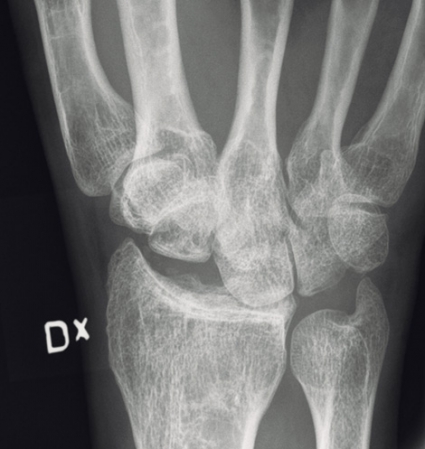

Observera att samtidiga ipsilaterala skador, t ex armbågsluxation, är vanliga. Akut karpaltunnelsyndrom förekommer i ungefär en tredjedel av fallen. Diagnosen ställs på röntgenbilden: Leta efter oordning bland karpalbenen och brutna Gilulas linjer! Observera att luxationen främst framträder på sidobilden, medan frontalbilden kan förefalla närmast normal. Man ska vara frikostig med datortomografi (DT), som kan påvisa mer ovanliga skademönster och synliggöra associerade karpala frakturer. Scaphoideum- och capitatum-frakturer är i detta sammanhang vanligast förekommande. DT kan också underlätta valet av snittföring. Observera att dessa skador alltid kräver öppen kirurgi, även om primär reposition lyckas och kontrollröntgen inte visar några frakturer. Enbart perkutan stiftfixation är aldrig till fyllest.